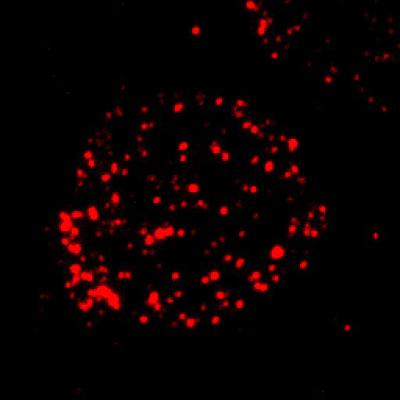

To identify the true FCMR gene, the UAB researchers used chronic lymphocytic leukemia cells as a source of this gene, since such leukemia cells are known to over-express the Fc mu receptor. This enabled researchers to identify the FCMR gene more efficiently.